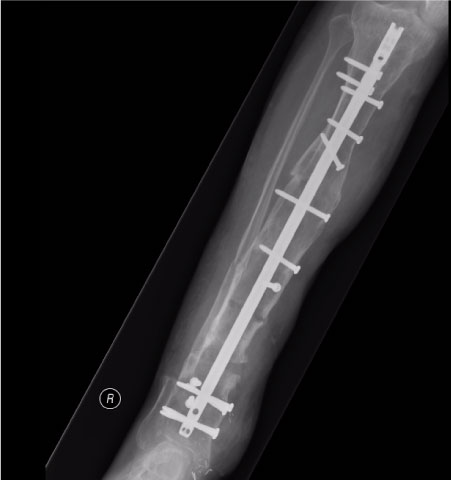

At 3 and 9 months post surgery, the patient reported no significant problems and at latest follow up, the soft tissue and tibia have gone on to heal clinically (Figure 2) and radiologically (Figure 3). The patient is delighted with the results and is now mobilising unaided once more and has returned to his full time occupation running multiple businesses.

Figure 3: Final post op X-ray after deformity correction. View Figure 3